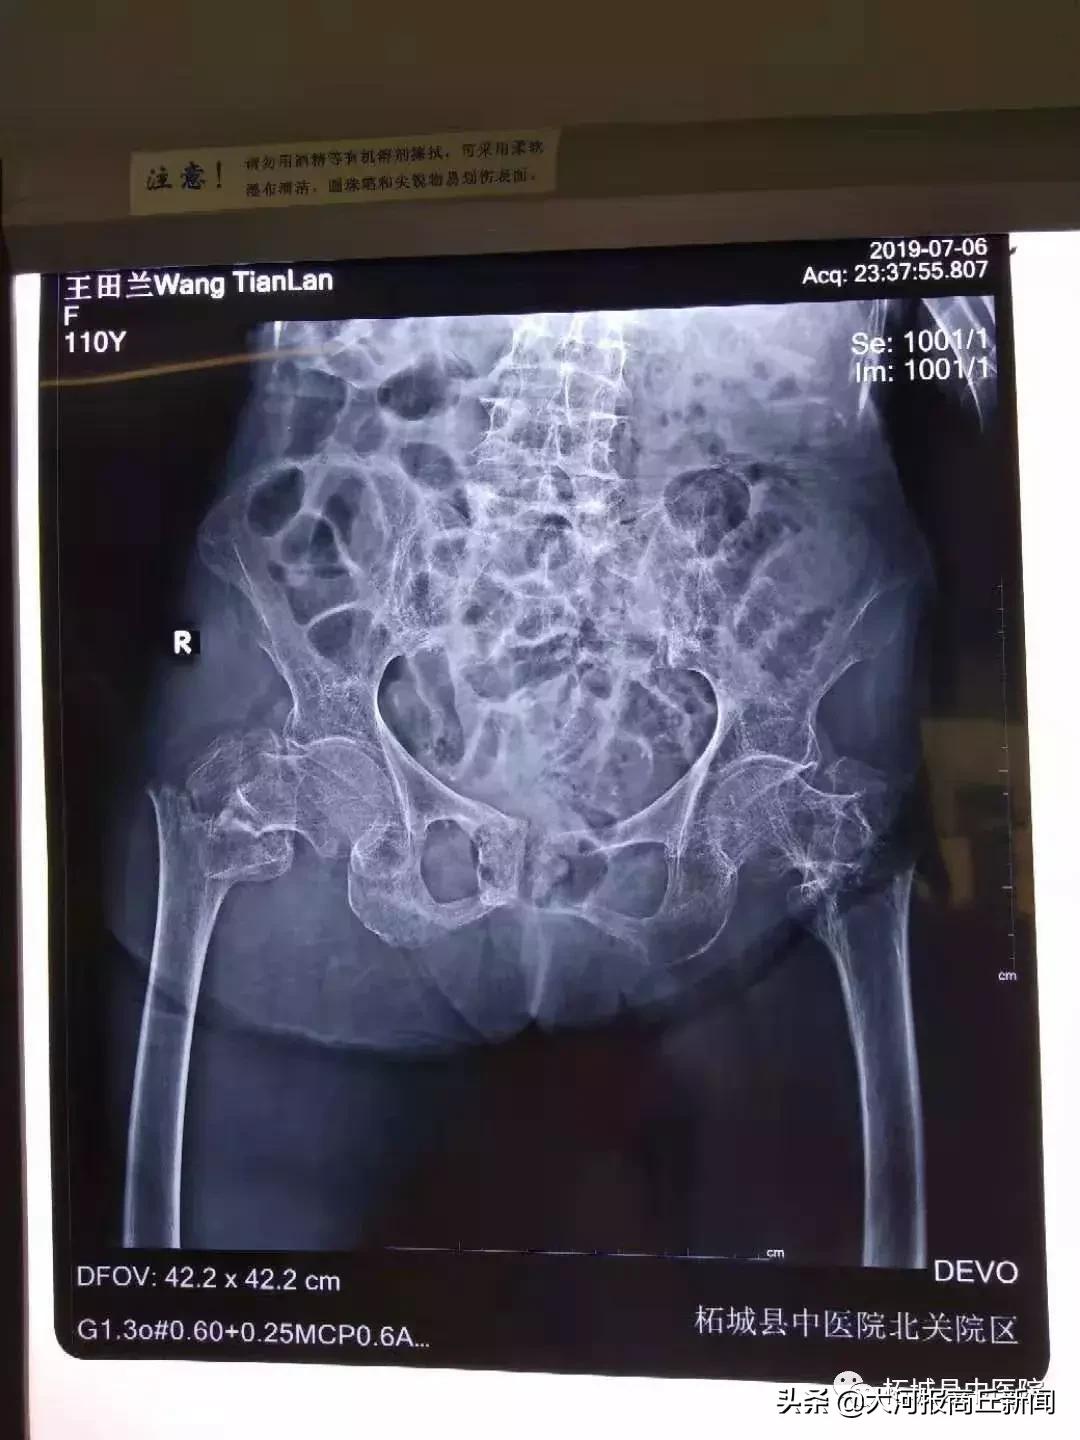

可天有不测风云,一天老人在家活动时不慎滑倒摔到右髋部,当时就感到局部疼痛、肿胀、活动受限,家人急忙把老人送到中医院北关院区找到骨科专家殷晓东寻求诊治,老人年事已高,殷晓东院长接诊后十分重视,第一时间仔细查体后,诊断为右股骨转子间骨折收住骨科。

该老人是一位基础疾病较多的患者,详细检查后,老太太骨折合并有贫血、低蛋白血症、慢性阻塞性肺炎,保守治疗需长期卧床,可能导致坠积性肺炎、褥疮、下肢静脉血栓形成、骨折不愈合等并发症威胁患者生命安全,请北关院区呼吸科王因仲主任、胸痛中心孙全立主任会诊评估,经过多番讨论和家属沟通,参考我院曾经做过多例百岁老人关节置换术后第二天下床走路病例,最终确定人工髋关节置换术的治疗方案。